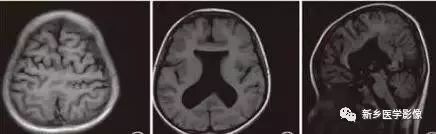

无脑回和巨脑回

无脑回和巨脑回是一组因神经元移行异常所致的脑回发育异常。巨脑回也称平滑脑。巨脑回指有部分脑回存在,这些脑回异常增大增宽、脑沟变浅。巨脑回主要位于额、颞部。无脑回主要位于顶、枕部。

临床上,无脑回和巨脑回畸形患儿均表现有小头畸形和轻微的面部异常,完全无脑回畸形常在两岁前死亡。不完全无脑回畸形通常能长期存活。

CT和MR均能够很好显示无脑回和巨脑回畸形,表现为大脑半球表面几乎呈光滑状,仅可见少数宽阔、粗大、平坦的脑回,脑沟缺如。脑灰质增厚、脑白质变薄,灰白质分界面异常平滑,见不到白质向灰质内伸入的现象。常见透明中隔腔存在,侧脑室扩大,蛛网膜下腔增宽。